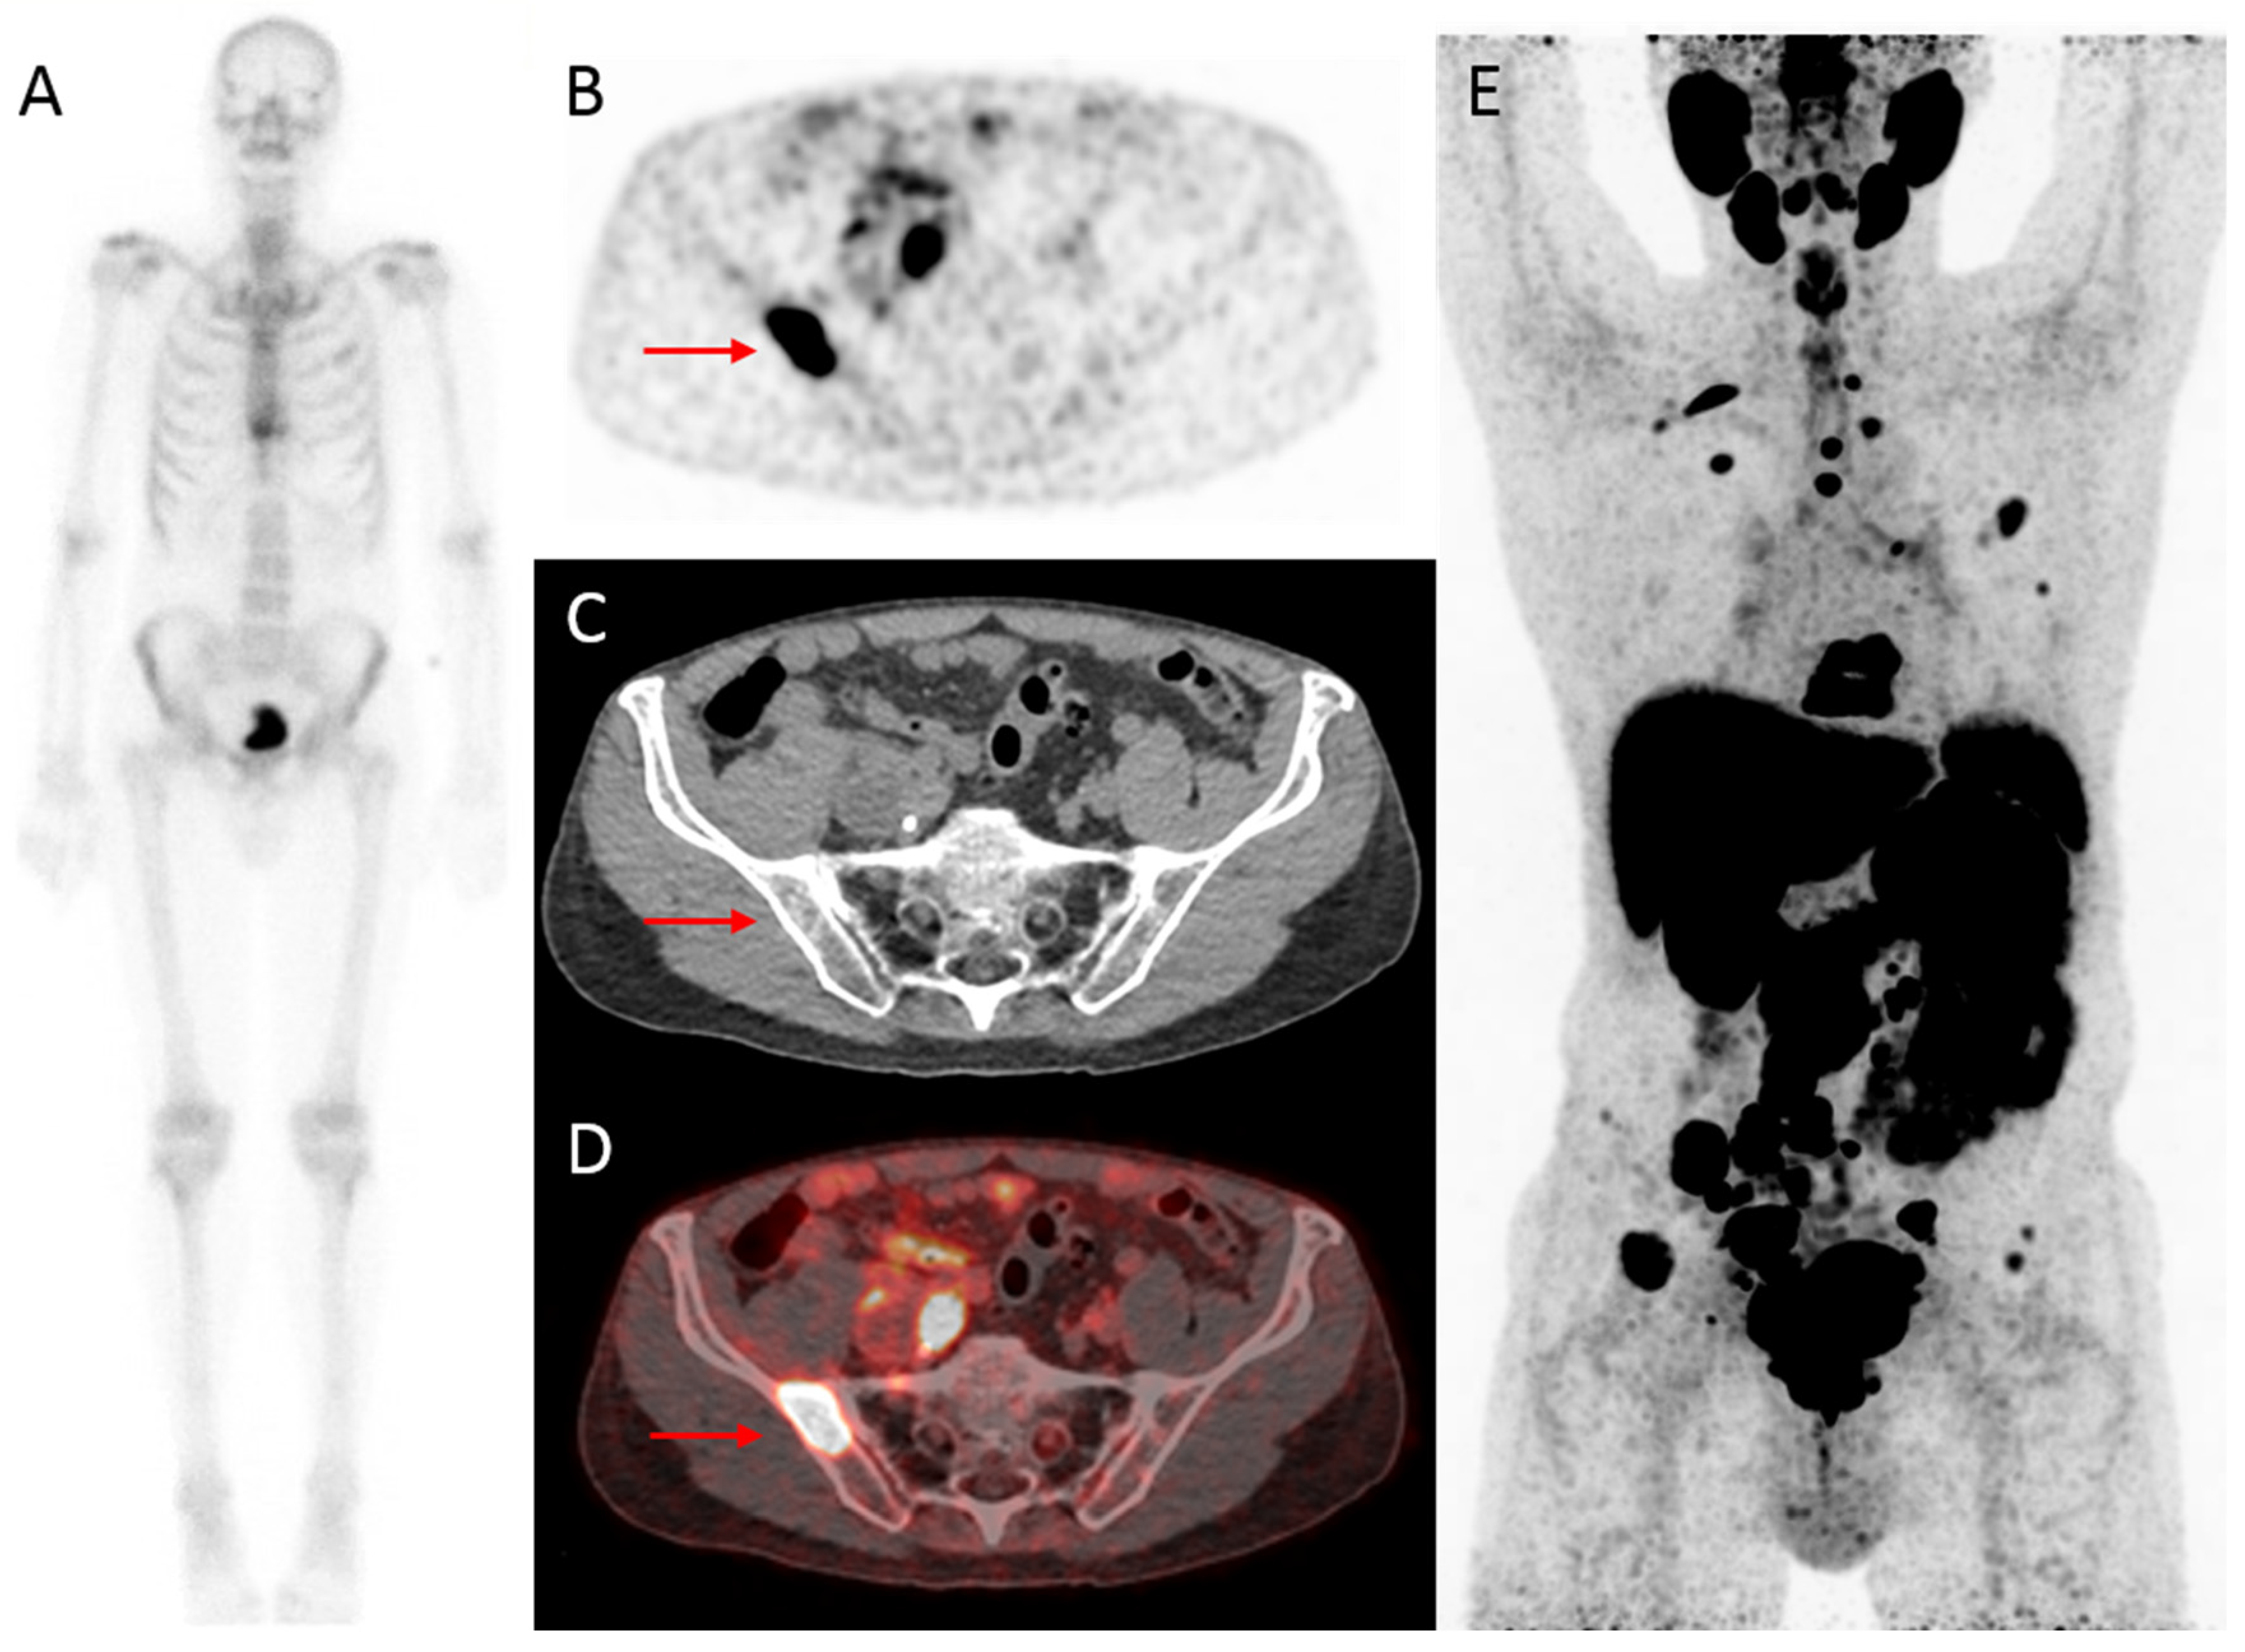

Figure 2.

Initial assessment of a 75-year old patient, newly diagnosed with PCa (Grade Group (GG) 5), with an initial PSA-value of 1396 ng/mL. On bone scintigraphy, the increased uptake in the thoracic spine was attributed to an (osteoporotic) collapsed vertebra, and the faint uptake in the left third rib to a post-traumatic origin. Despite the high PSA-value, no abnormal uptake consistent with osseous metastases was visualized (A). However, extensive metastatic disease was found on 18F-DCFPyL PET/CT (B–E). For example, transversal 18F-DCFPyL PET (B) and fused PET/CT (D) showed highly increased PSMA-expression in the right iliac bone (red arrow, maximum standardized uptake value (SUVmax) 8.15), compatible with a lytic lesion on CT (C). The time interval between bone scintigraphy and 18F-DCFPyL PET/CT was 5 days.